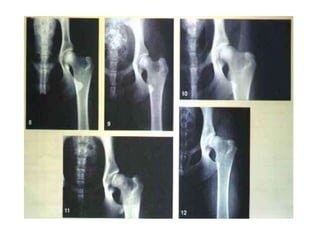

SINCONDROSES Os ossos de uma articulação do tipo sincondrose estão unidos por uma cartilagem hialina. Muitas sincondroses são articulações temporárias, com a cartilagem sendo substituída por osso com o passar do tempo ( isso ocorre em ossos longos e entre alguns ossos do crânio). As articulações entre as dez primeiras costelas e as cartilagens costais são sincondroses permanentes.

Sincondroses pós-cranianas:- Epifisiodiafisárias;- Epifisiocorporal;- Intra-epifisária;- Múltipla;- Esternais;- Manúbrio-esternal;- Xifoesternal;- Sacrais.

SINCONDROSES Os ossosde uma articulação do tipo sincondrose estão unidos por uma cartilagem hialina. Muitas sincondroses são articulações temporárias, com a cartilagem sendo substituída por osso com o passar do tempo ( isso ocorre em ossos longos e entre alguns ossos do crânio). As articulações entre as dez primeiras costelas e as cartilagens costais são sincondroses permanentes.

Sincondroses pós-cranianas:- Epifisiodiafisárias;-Epifisiocorporal;- Intra-epifisária;- Múltipla;- Esternais;- Manúbrio-esternal;- Xifoesternal;- Sacrais.